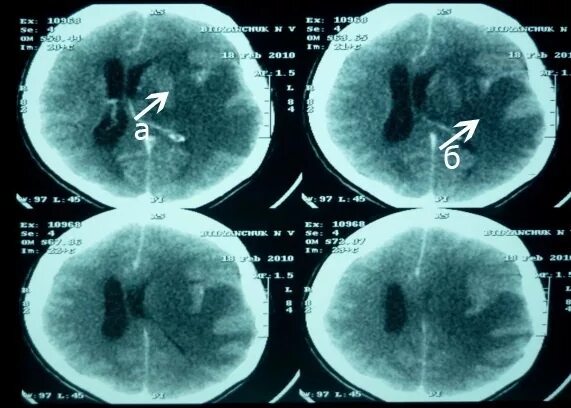

50 лет кт